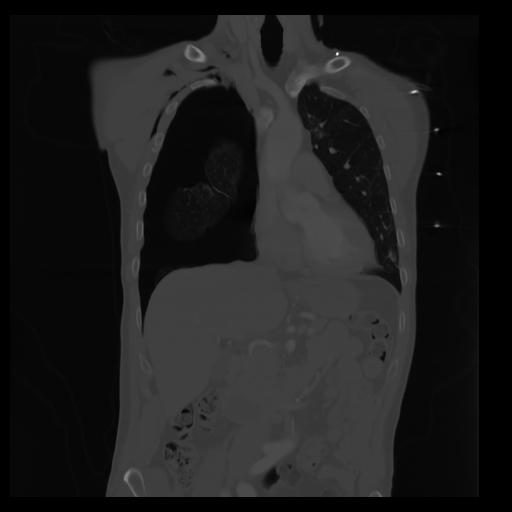

29 CUERPO,CE,Coronal,3.000,CUERPO,Coronal,